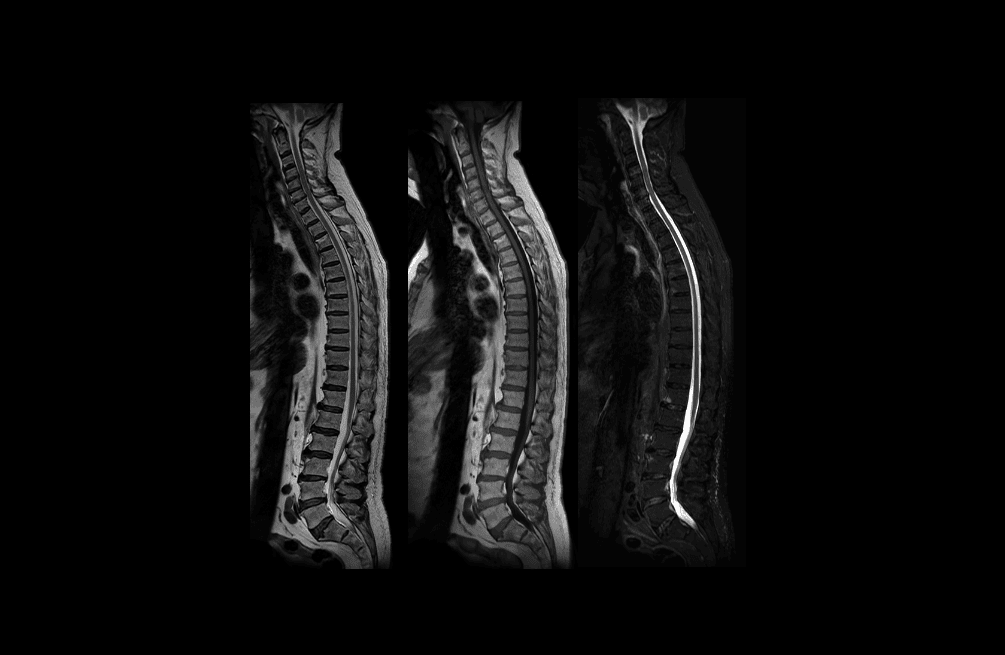

Eksempler på MR-scanninger

- Hjerne, rygmarv og hele rygsøjlen (centralnervesystemet)

- Blodkar og knogler